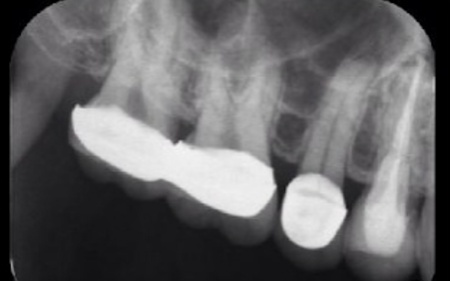

40代女性 炎症を起こした右上奥歯にマイクロスコープを用いた精密根管治療を行った症例

拝見したところ、右上奥歯(第2小臼歯)には保険診療の白い被せ物であるCADCAMが装着されていました。

レントゲン撮影をして検査すると、その手前の右上奥歯(第1小臼歯)には神経や血管が通る根管に清掃と消毒を行う根管治療が施されていました。しかし、歯の内部に細菌が侵入して炎症を起こし、歯根の先に膿が溜まる根尖病巣(こんせんびょうそう)を発症している状態です。

レントゲン撮影で根尖病巣の治癒を確認後、最終的な被せ物を作製するため、歯の形を整えてから型取りを行います。

後日、完成したセラミッククラウンを装着し、噛み合わせや見た目に問題がないかを確認して、治療を終了しました。